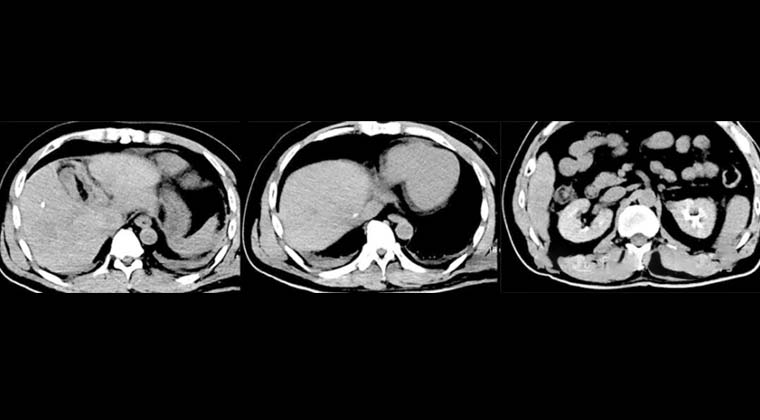

② Случай 2:

Пациент: мужчина, 53 года, злокачественная опухоль печени

(предпроцедурная визуализация)

(визуализация сразу после процедуры)